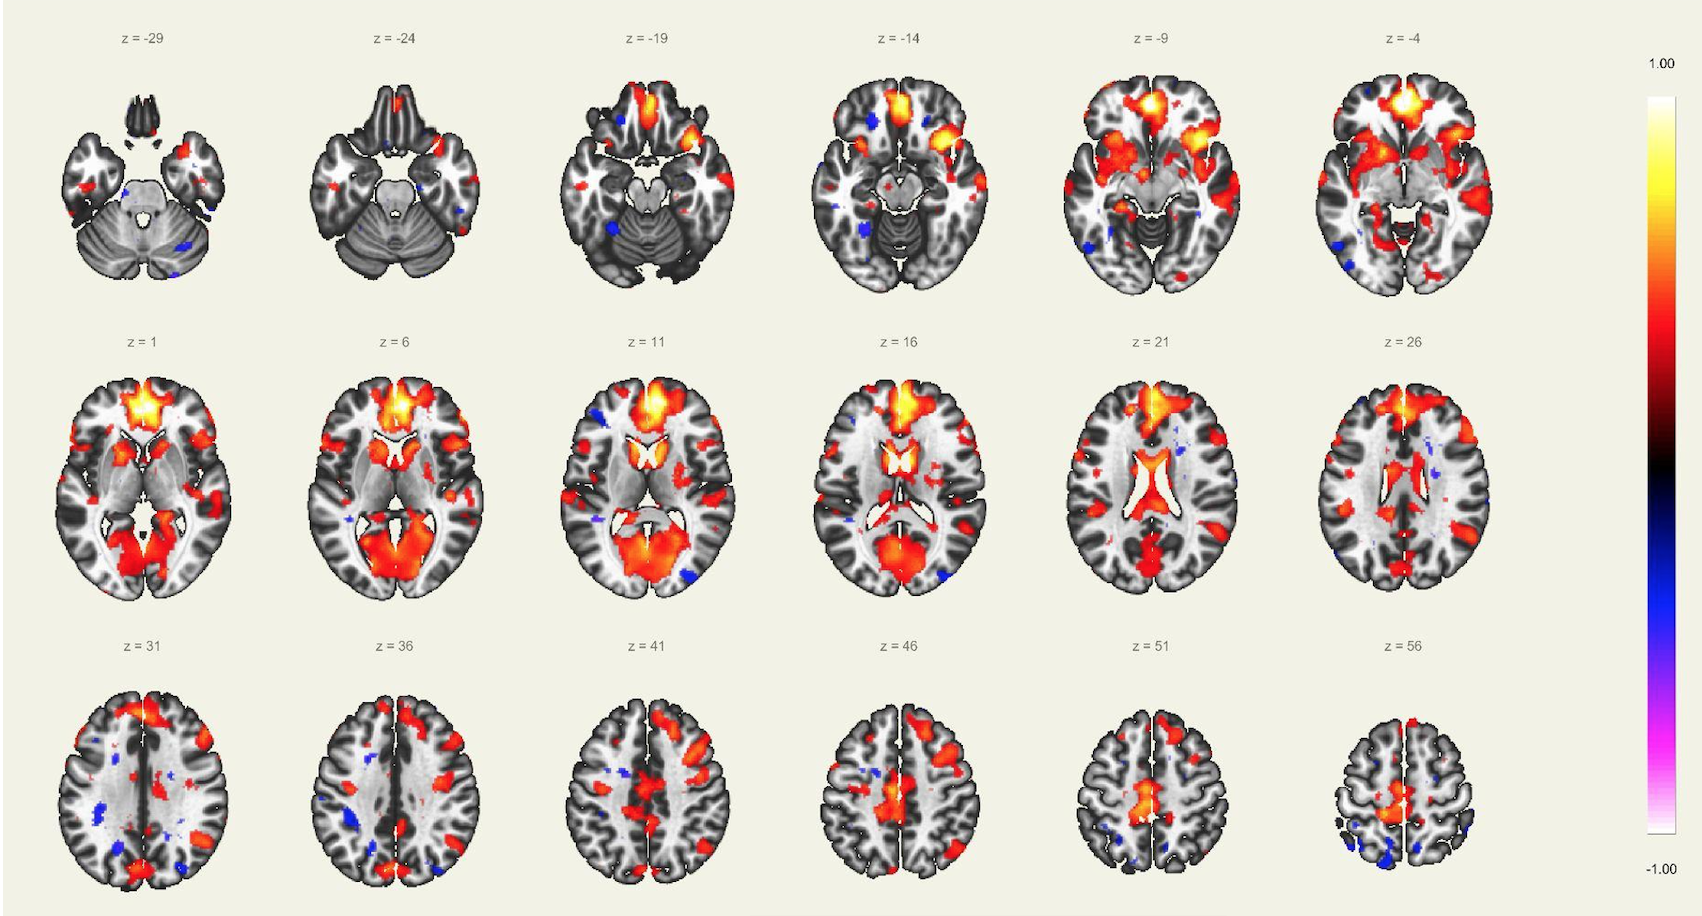

En este estudio, el escaneo se realizó con un resonador de 3 Tesla del servicio de diagnóstico por imágenes de la Clínica Internacional, a un paciente joven, sin comorbilidades ni antecedentes de importancia, el cual estuvo despierto en todo momento y con los ojos cerrados. Además, se le dio instrucciones de completar palabras mentalmente sin emitir sonido alguno o hacer gestos, llegando a identificarse las distintas redes cerebrales detalladas posteriormente.

El estudio fue realizado con secuencia BOLD, con los siguientes parámetros: cortes: 40, factor de distancia: 0%, Field of View: 240 mm, grosor de corte: 4 mm, tamaño de vóxel: 3.8 x 3.8 x 4 mm, TR: 3000 ms, TE: 30 ms, Umbral: 4 y tamaño del paradigma 20.

A pesar de la ausencia actividad física, resulta imposible indicar que no se esté realizando ningún tipo de actividad mental, como recuerdos o el uso de la imaginación. La consecuencia de esto se ve reflejada en los cambios de la actividad neuronal.16 A través de este método de vóxel semilla se ha logrado identificar distintas redes de conectividad funcional descritos a continuación:

Red “Modo por Defecto”:

Involucra la corteza cingular posterior, corteza prefrontal medial y la corteza parietal lateral. La actividad de esta red se ve incrementada en el caso de que la persona en estudio esté en una condición de reposo, observándose una especie de desactivación al realizar algunas tareas. Esta red tiene participación también en algunos aspectos sociales como la introspección, divagación, procesamiento emocional, entre otros.

Red Precuña:

Área asociada con la red “modo por defecto”, caracterizada con zonas de alta tasa metabólica comparado con otras redes durante el estado de reposo. Se ha reportado la importancia de esta área, interviniendo en funciones de comportamiento; así como en la manipulación de imágenes mentales y atención guiada internamente, derivada del estudio de imágenes visuoespaciales.

Red del Lenguaje:

Implica las regiones prefrontales, temporo-parietal y subcortical, además de las ya conocidas áreas de Broca y Wernicke. El habla, el entendimiento, lectura, interpretación, mímicas; son algunas de las funciones más importantes de esta red. Adicionalmente, el área de Broca es asiento de las neuronas espejo, las cuales intervienen en el entendimiento e imitación de actividades motoras.

Red Sensorio-Motora:

Primera red en ser estudiada usando el método de vóxel semilla, la cual muestra la alta correlación entre las regiones motoras del hemisferio izquierdo y derecho. En esta corteza sensorio-motora, las áreas de Broddman, localizadas en la región posterior al surco central, el giro precentral y la corteza auditiva primaria, forman parte de esta red, en asociación con los núcleos ventral laterales y ventral posterior del tálamo. La activación de esta red interviene directamente en la percepción de estímulos sensorio-motores, auditivos y en el planeamiento y ejecución para el movimiento de los músculos.